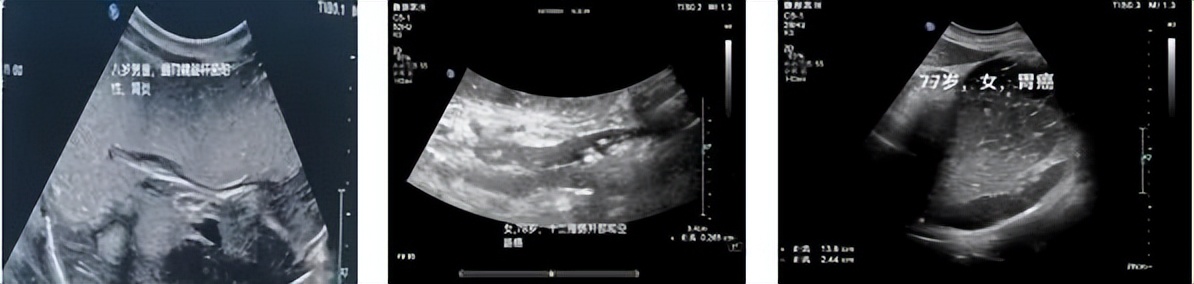

胃超声造影能够检查出的病症:

1.肿瘤性病变:胃癌、胃息肉、胃间质瘤、十二指肠肿瘤等。

2.炎性与溃疡性病变:急、慢性胃炎、胃及十二指肠溃疡等。

胃超声造影检查与胃镜是最完美的合作关系。胃超声造影检查是胃镜禁忌症最好的补充检查方法,胃超声造影检查是一种断面显像技术,把胃壁分为七层断面,每层断面有无病变均能清晰显示,把胃充盈作为透声窗,增强了整个腹部的连贯性,可以观察胃周围毗邻器官的病变,可以与相邻器官疑似病变进行诊断与鉴别诊断拓宽了临床的诊断视野,为临床提供丰富的诊断信息。

胃超声检查技术对粘膜下层病变非常敏感,对间质瘤、外生性病变显示清晰,是胃镜的有益补充。运用胃肠超声测量病变的浸润大小、深度与范围、有无淋巴结的转移、局灶性的病变是囊液性结构还是实性结构,所以胃镜发现的阳性患者更应该做胃超声复查。